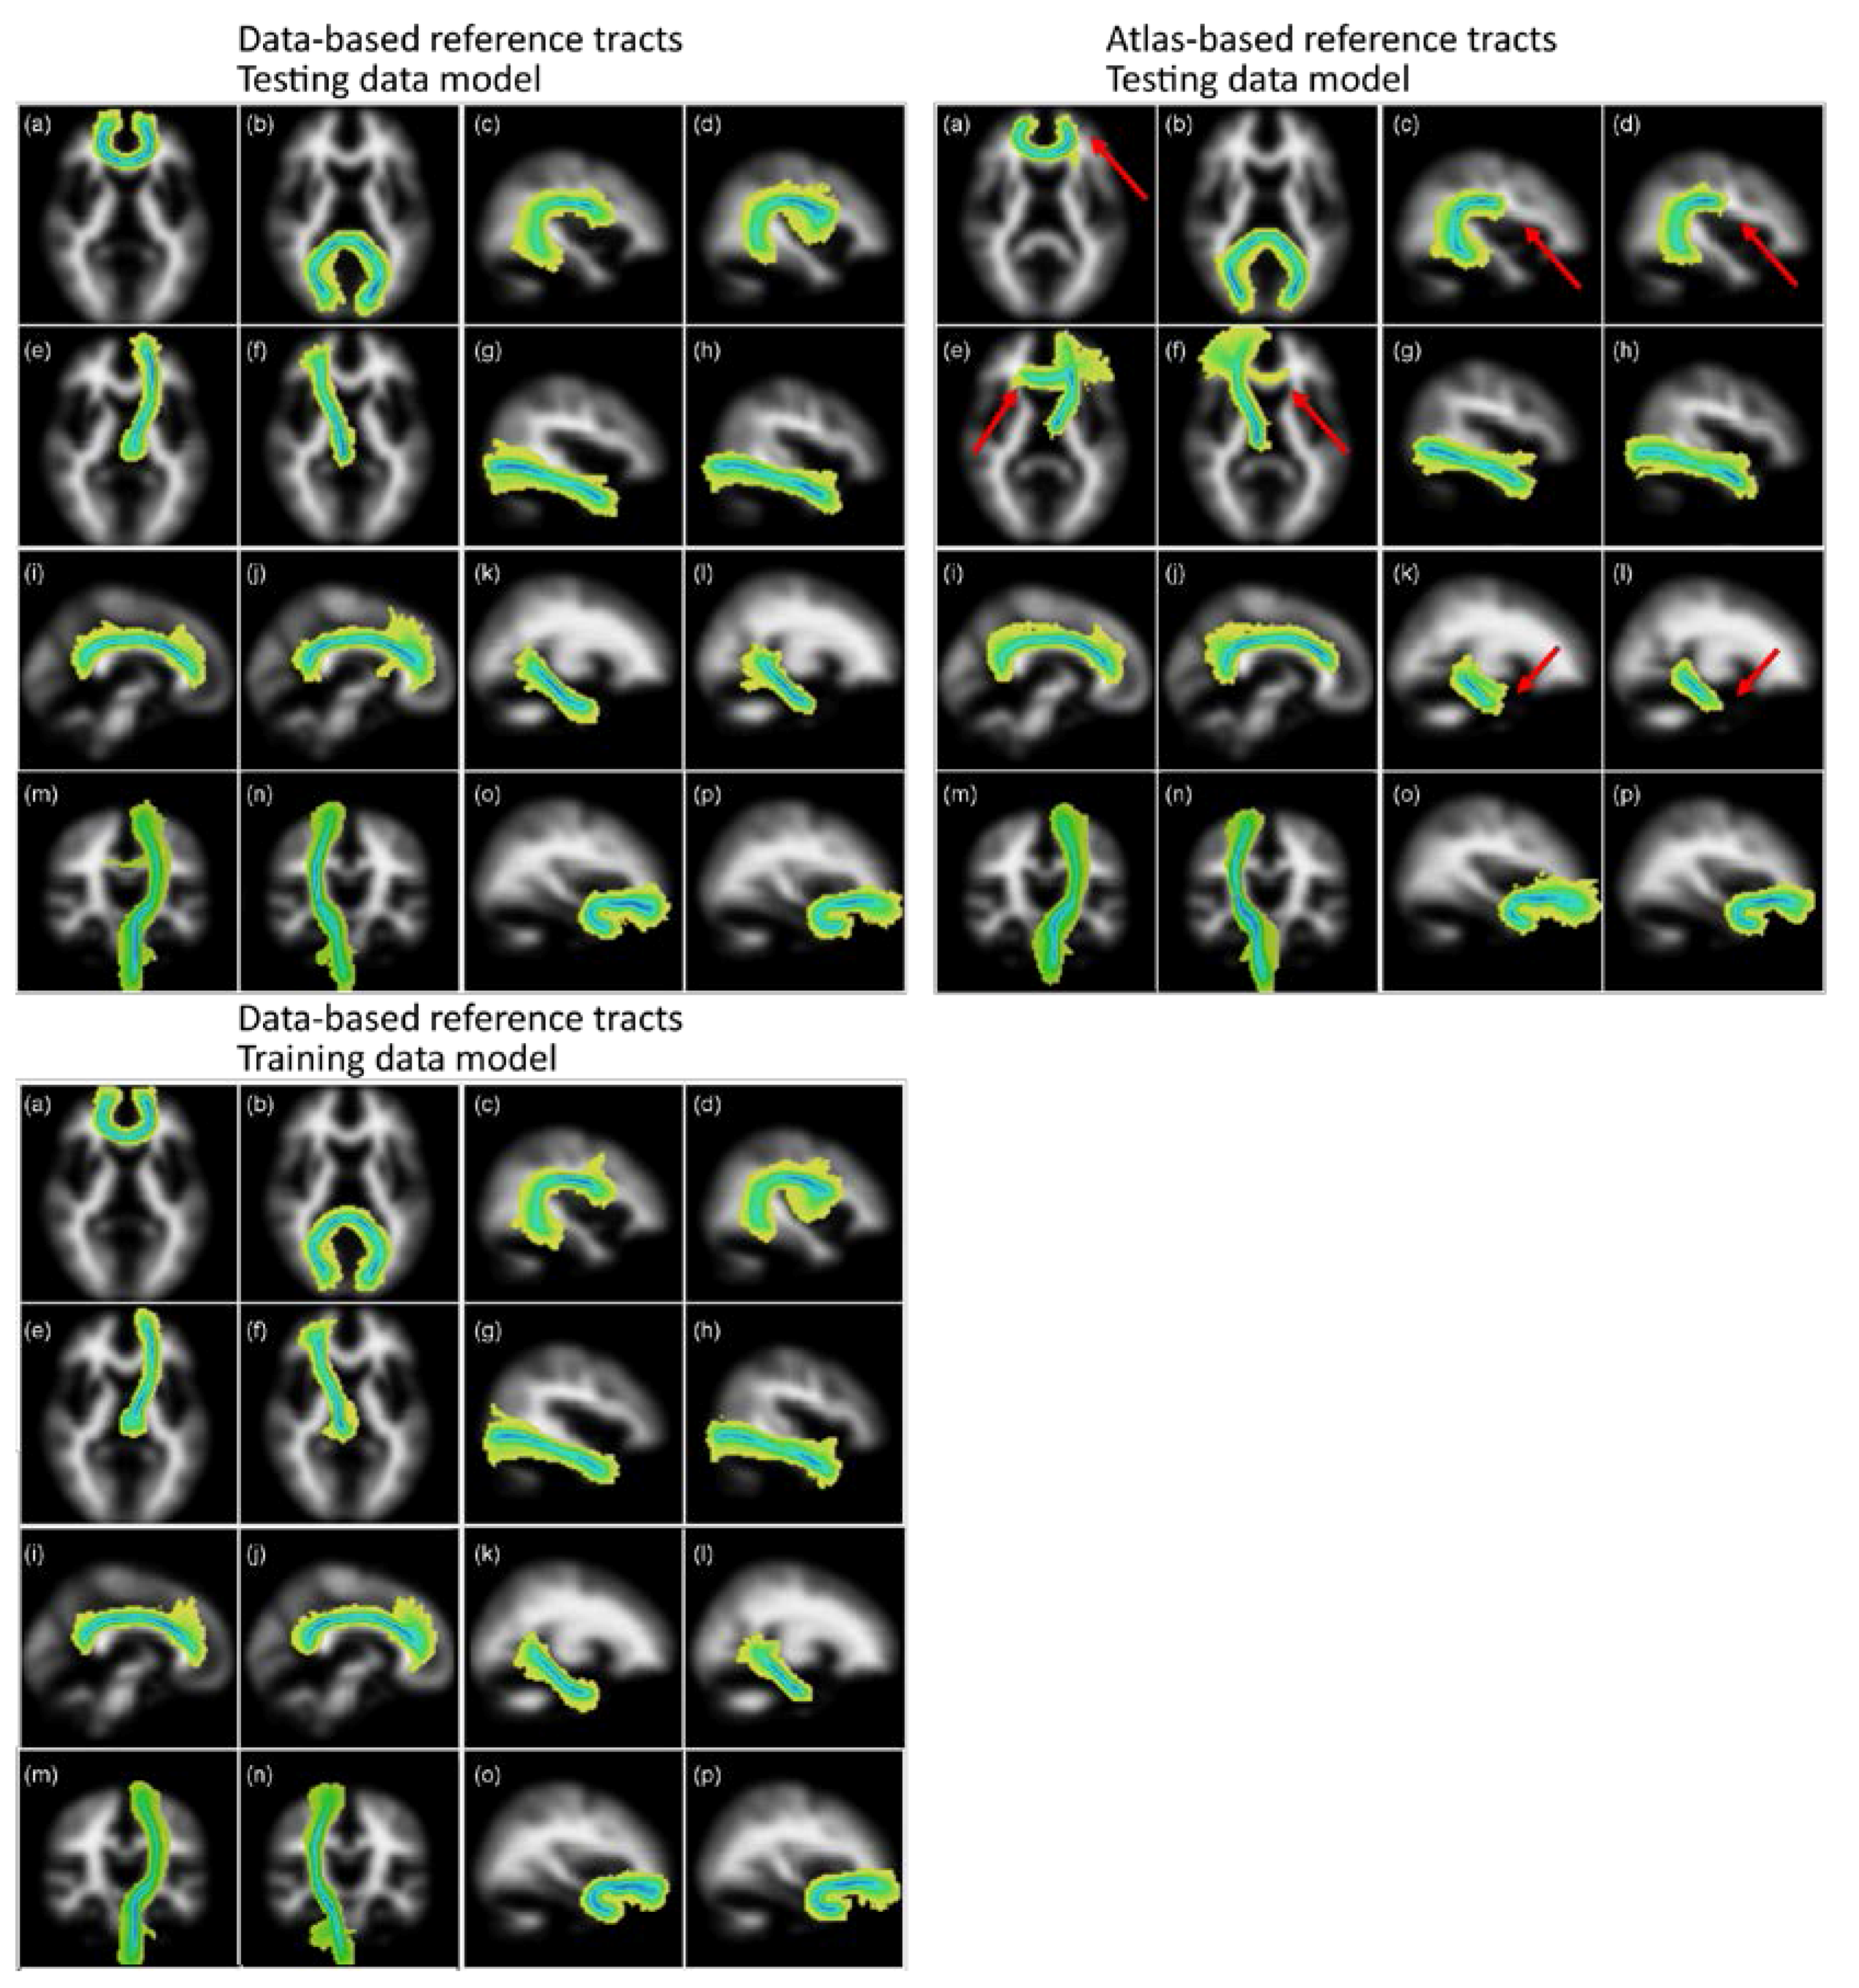

Figure 4 shows the group maps that were created by overlaying the segmented tracts from the 50 older age volunteer LBC1936 dataset into standard brain MNI space as maximum intensity projections. These images show that the segmentations obtained from the two sets of reference tracts are similar, except for the left and right ATR, where many of the segmentations using the atlas-based reference followed the wrong path, thereby failing the visual check. Some small differences are, however, obvious in other tracts, specifically regarding their lengths. In particular, the segmentations of the corpus callosum genu, the arcuate fasciculi, and the ventral cingula were longer when using the new data-based reference tracts, with more of the tract being included in the segmentation.

Figure 4.

Group maps projections for the 16 tracts of interest segmented using the data-based (left panel) and atlas-based (right panel) reference tracts. Top panels used a matching model trained in the LBC1936 data, and the bottom panel used a model trained in the training data. The tracts represented are: (a) genu and (b) splenium of the corpus callosum, left and right arcuate fasciculus (c,d), left and right anterior thalamic radiation (e,f), left and right inferior longitudinal fasciculus (g,h), left and right dorsal (i,j) and ventral (k,l) cingulum, left and right corticospinal tracts (m,n) and left and right uncinate fasciculus (o,p). Color scale represents the voxel visitation frequency, from 1 (light yellow) to 50 (dark blue). Maps are projected into the plane of the voxel with maximum visitation value. Red arrows point at the main differences obtained between the resulting tracts derived from atlas-based and data-based reference tracts. Figure adapted from [1].

The group maps from tracts that were generated with each training model showed that the choice of training model had a modest effect on the segmented tracts.